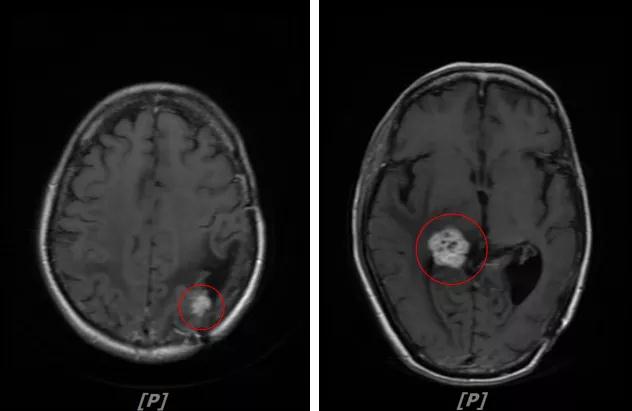

6.病情第5次进展:2020年5年患者头痛等症状进一步加重

头颅增强MR:左侧顶叶皮层区见不规则片状T1WI低信号、T2WI高信号影,病灶大部信号接近脑脊液,增强后无强化,其边缘见结节样明显强化影,平扫近似等信号,大小约12x12mm,较2020-02-11MR老片略增大,左侧脑室三角区不均扩大;右侧颞叶-丘脑区见结节样T1WI等低信号、T2WI不均匀高低混杂信号影,增强后不均匀明显强化,大小约24x23x26mm,较前片增大,似见累及胼胝体压部;两侧半卵圆区、侧脑室旁、基底节区及右侧丘脑、颞叶见融合团片状T1WI低信号、T2WI及Flair高信号影,增强后未见明显强化,较前片相仿;余脑室、脑池、脑沟大小形态可,中线结构向左偏移。左侧乳突区见T2WI高信号影充填。

颅脑转移瘤治疗后观

左顶叶强化结节、右侧颞叶-丘脑区结节影:较前片增大

幕上脑白质融合异常信号:符合放疗后改变